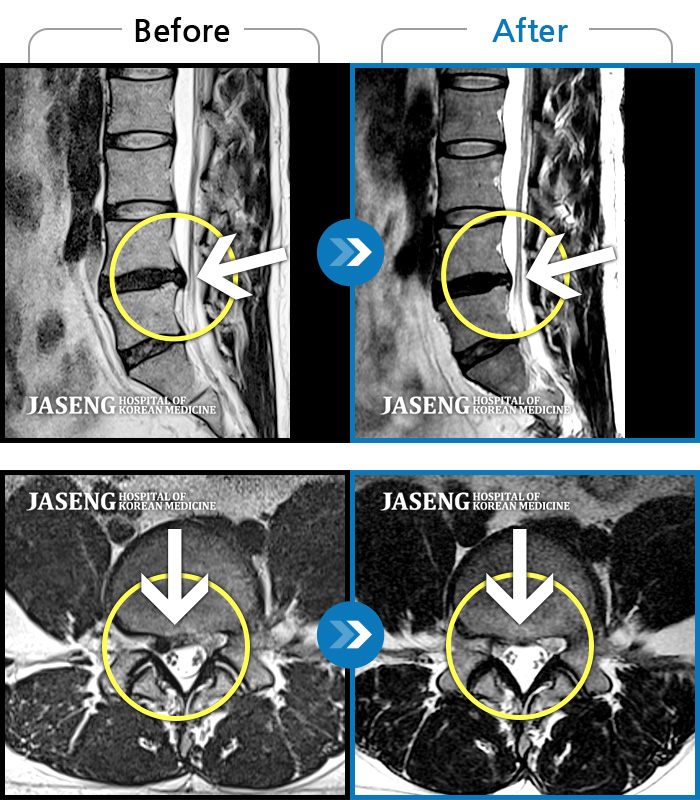

푸쉬업을 여러 번 반복한 뒤 극심한 하요부 통증 및 우측 하지부 저림

2024.03.21 ~ 2024.09.23